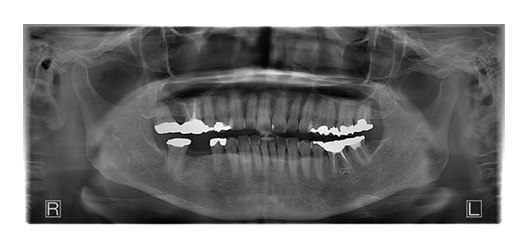

CASE_04

60代女性(インプラント)

- 患者さん情報(年齢・性別)

- 60代 女性

- 主訴

- 左下のインプラントを考えているが、怖い

- 治療箇所

- インプラント1箇所、セラミック3箇所

- 治療方法

- インプラント、セラミック治療

- 費用

- インプラント42.9万円、セラミック治療約24万円

- 治療期間

- 約1年6か月